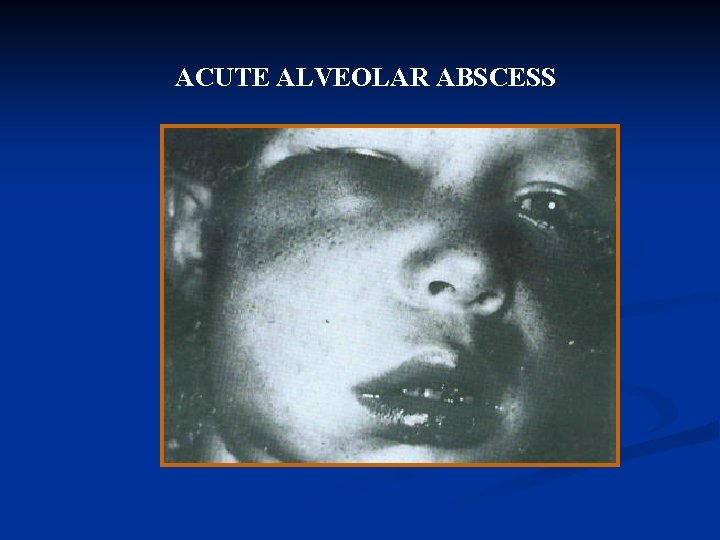

ACUTE ALVEOLAR ABSCESS

Definition: An acute alveolar abscess is a localized collection of pus in the alveolar bone at the root apex of a tooth following death of pulp

Symptoms: Initially slight tenderness of the tooth. Later - severe throbbing pain, swelling of the overlying soft tissues.

As the infection progresses- and extends beyond the original site. painful, becomes more tooth The elongated, and mobile. while the adjacent tissue continuous to swell.

osteitis, periostitis, cellulitis, or osteomyelitis. The contained pus may break through to form a sinus tract, usually opening in the labial or buccal mucosa. such as the skin of the patient’s face or neck, or even the antrum or nasal cavity.

ulting becomes swelling extensive, the When cellulitis may distort the patient’s appearance grotesquely.

The patient may appear pale, irritable and weakened from pain and loss of sleep. Patients with mild cases may have only a slight rise in temperature (90 to 1000 F).